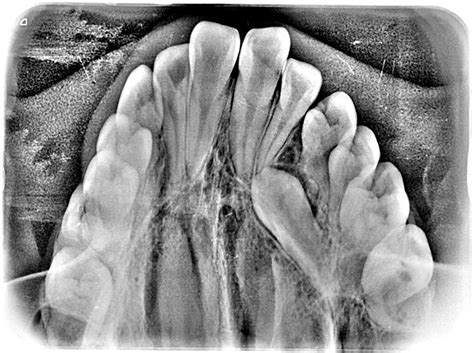

Resultados Radiográficos

En la ortopantomografía observamos un adecuado paralelismo radicular con gérmenes de cordales en formación y con suficiente espacio habitable. También observamos imágenes radiolúcidas de caries oclusales en molares inferiores. La telerradiografía lateral de cráneo muestra una normoclusión con perfil armónico (figs. 15 y 16).

Figura 15. Ortopantomografía postratamiento.